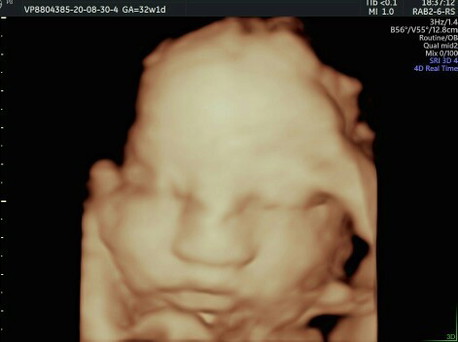

Perjuangan banget nih pak dokternya biar dpt capture wajahnya si utun, sampe momi ikut gemes jugak soalnya utun ngajak main cilukba mulu.. 😅 Buat bunda-bunda yg masih galau sama biaya usg 4d bisa nih ke halobumil, nyesel banget dah soalnya baru tau kalo semurah ini pas hamil udh mau masuk 24w, udah gitu dokternya ramah dan sabar banget, jelasinnya detail, jd buat bunda-bunda yg baru pertama hamil, ini rekomended banget. #sharingiscaring